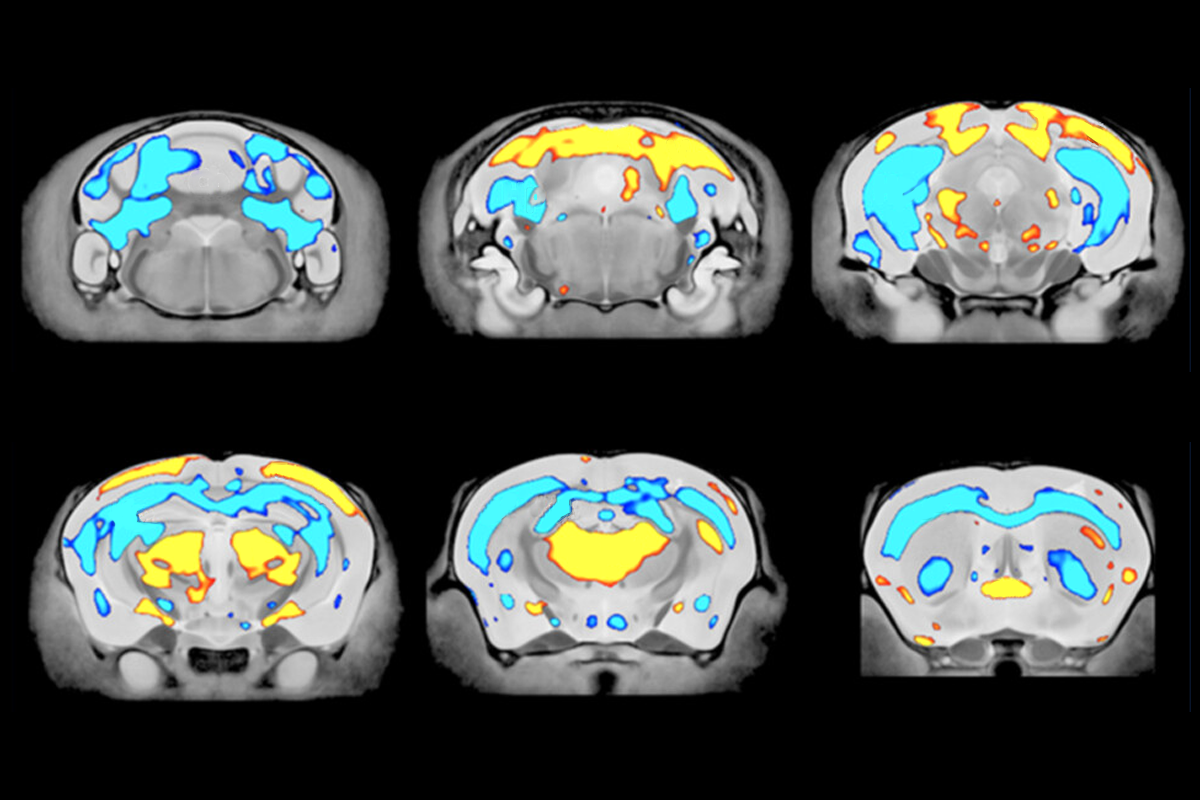

- “Altered brain structure in an ATRX-deficient mouse model of autism spectrum disorder” Autism Research